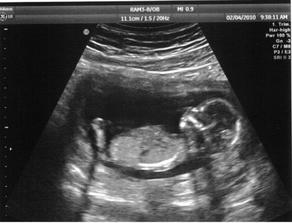

20.týden - UTZ biometrie ok, už je to pořádnej Mimísek 🙂, kontrola myomu, bohužel roste(5 cm), snad to opět dobře dopadne !

Máme další fotečku ! Brouček je roztomilý 🙂 Bude se jmenovat SEBASTIAN🙂